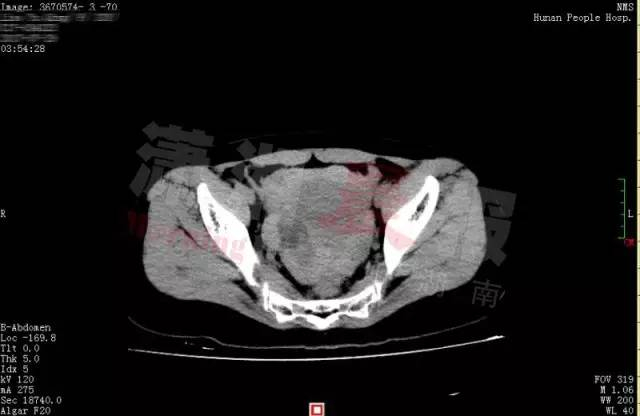

谁知激情过后,小晴出现下腹部疼痛,而且越痛越厉害,只得来到湖南省人民医院天兴阁院区急诊科就诊。尿妊娩检查结果为阴性,而腹部 CT 提示盆腔、腹腔有大量积血、积液,随即转入妇科。

黄主任立即为小晴进行诊断性腹腔镜手术,术中发现腹腔内积血约 1500ml,接近她全身总血量的 40%," 再晚一点来,就会危及生命了 "。医生还发现,在她右侧卵巢有一个直径 3cm 左右的黄体囊肿表面有破口,破口有血块附着,还有活动性出血。黄薇立即为她施行黄体囊肿剥除和创面缝合止血手术,恢复了卵巢的正常形态。